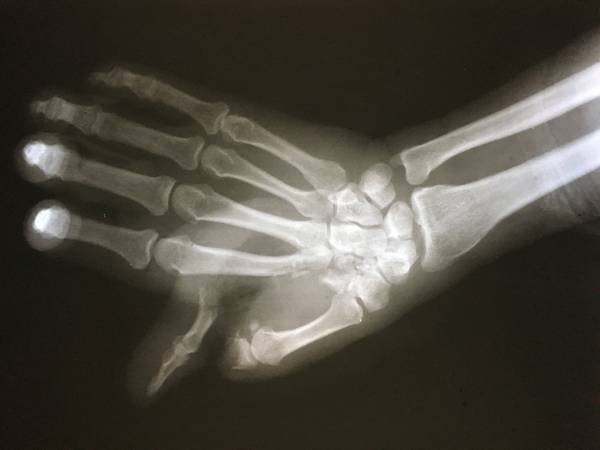

[断指再植] 一例断指断掌断腕?

整体还行,没有缺损,都是直接吻合没有移植